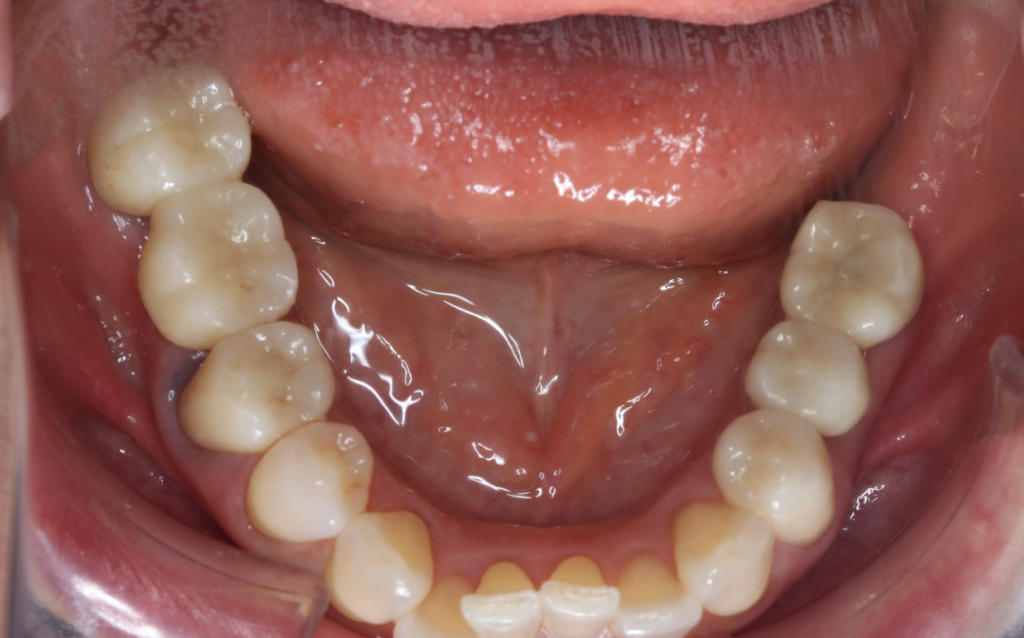

インプラント症例①

年齢 70代男性

治療期間 4ヶ月

インプラントメーカー ジンマーインプラント

治療内容 カスタムアバットメント、上部ジルコニア

治療箇所 右下5番、6番

治療費用 700,000円